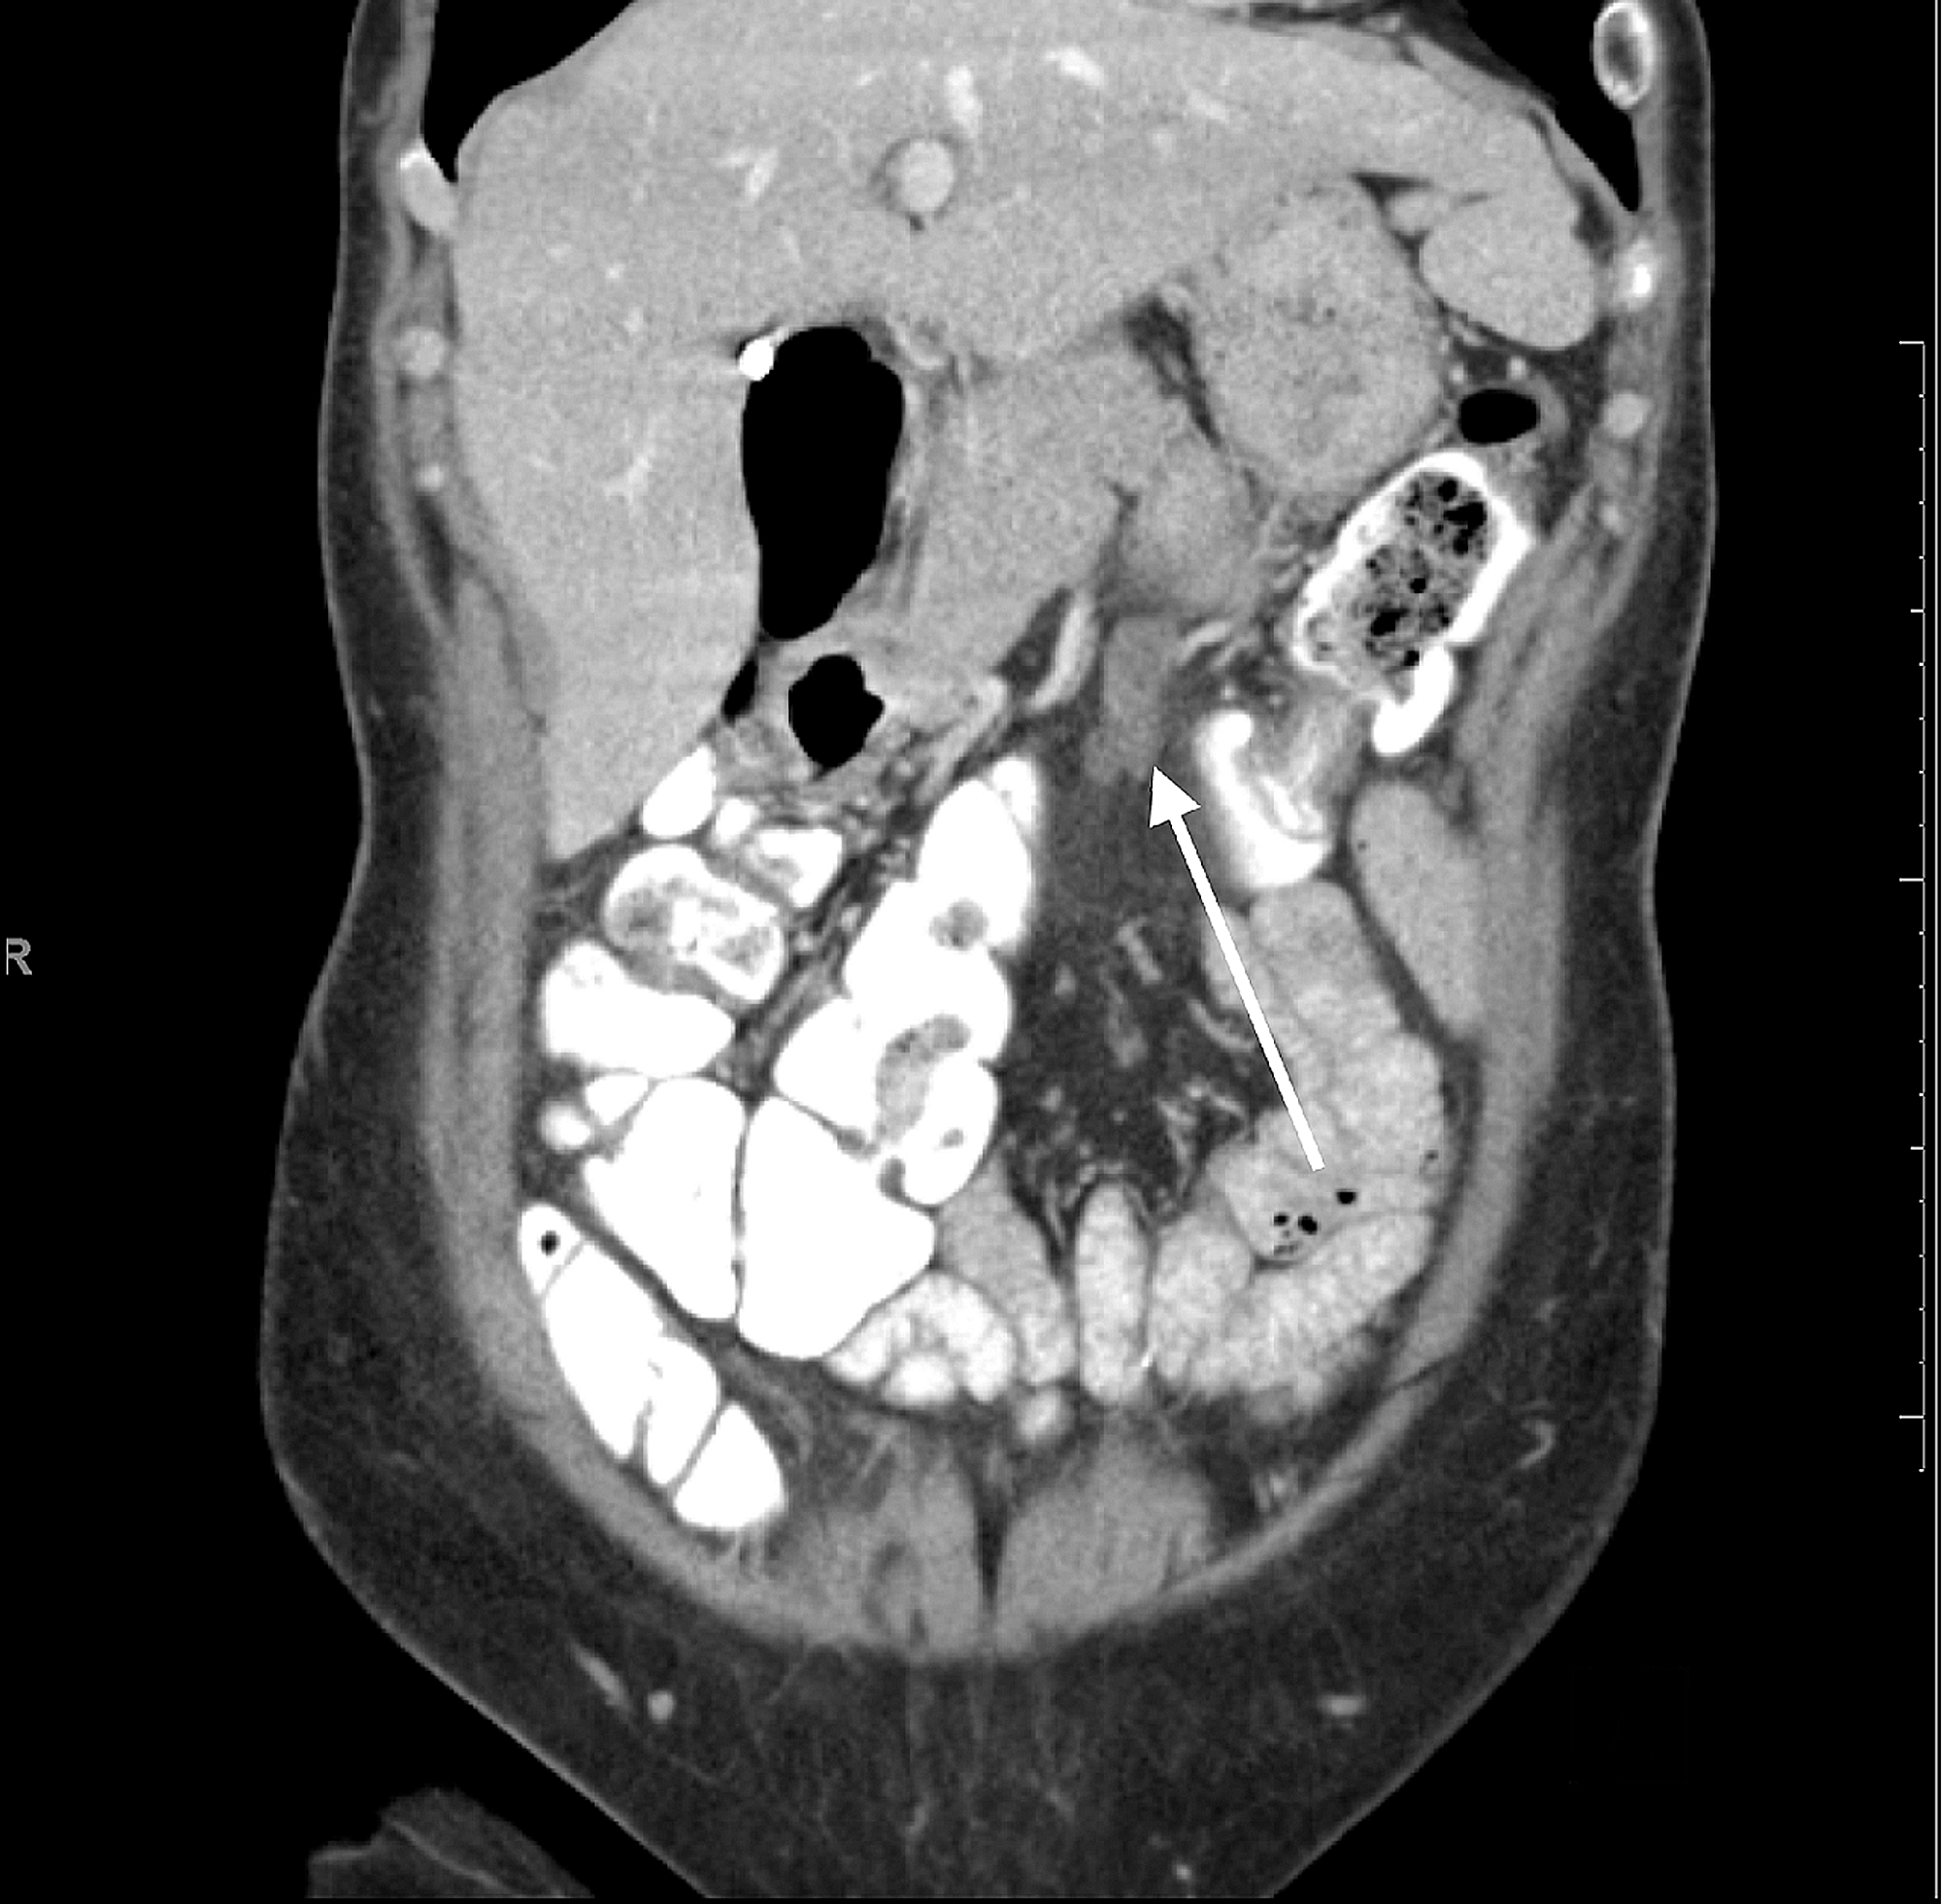

CT enterography Mesenteric hypervascular lesion in the mid ileum

CT enterography Mesenteric hypervascular lesion in the mid ileum Chalky White Lesions In Mesentery pathologic conditions of the mesentery can present a diagnostic challenge for radiologists because many. photograph of an axial image of the abdomen obtained on computerized axial tomographic (ct) assessment of a. sclerosing mesenteritis is a rare disease of the mesentery. the white chalky deposits are the saponificated remains of the fat in the mesentery and around. Chalky White Lesions In Mesentery.